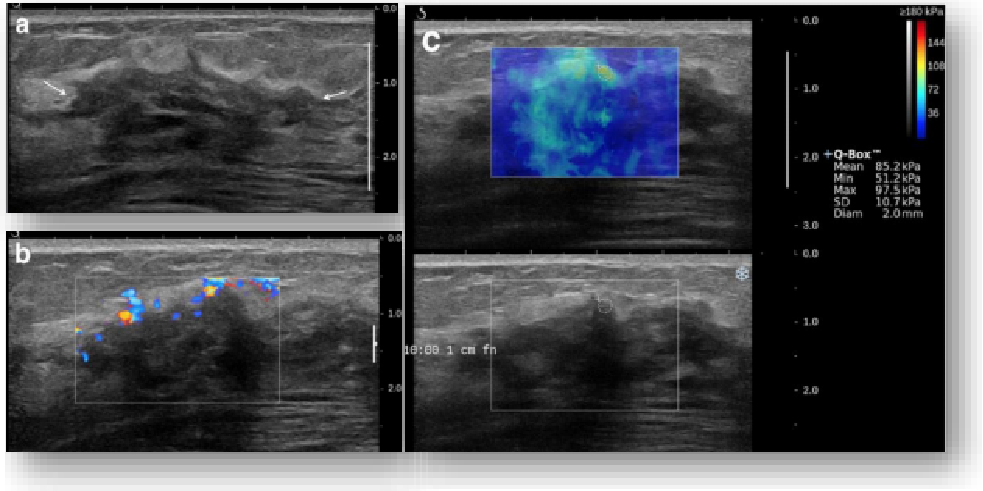

平面波超微细血流显像

能够提供更多真实的组织细小及末梢血管的血流信息,直观的观察组织内部的血管架构及血流形态的情况,提供临床更多有价值的诊断信息。

临床应用:

肿瘤鉴别诊断(肝脏、肾脏、甲状腺、乳腺、  涎腺等)

淋巴结评价(炎症、肿瘤)

肌骨系统临床诊断和疗效监测(关节、滑膜、韧带、肌肉炎症、 损伤等)

斑块内新生血管评估

超声介入术前进针方案提供血流参考信息

超声介入术后疗效评估

image.png

实时剪切波弹性成像

评估组织的软硬,并且提供定量数值,从而提示组织的良恶性。

鉴别诊断、精准分级、定量评价、穿刺引导、疗效评估、随访观察

恶性占位常常向周边组织进行侵润及扩散,二维很难观察到浸润部分的边界。使用实时剪切波成像能够对占位及周边组织进行硬度评估,通过颜色编码来区分不同组织的硬度信息,直观的观察占位组织的边界信息,更方便区分占位组织和正常组织的边界,准确评估消融范围。